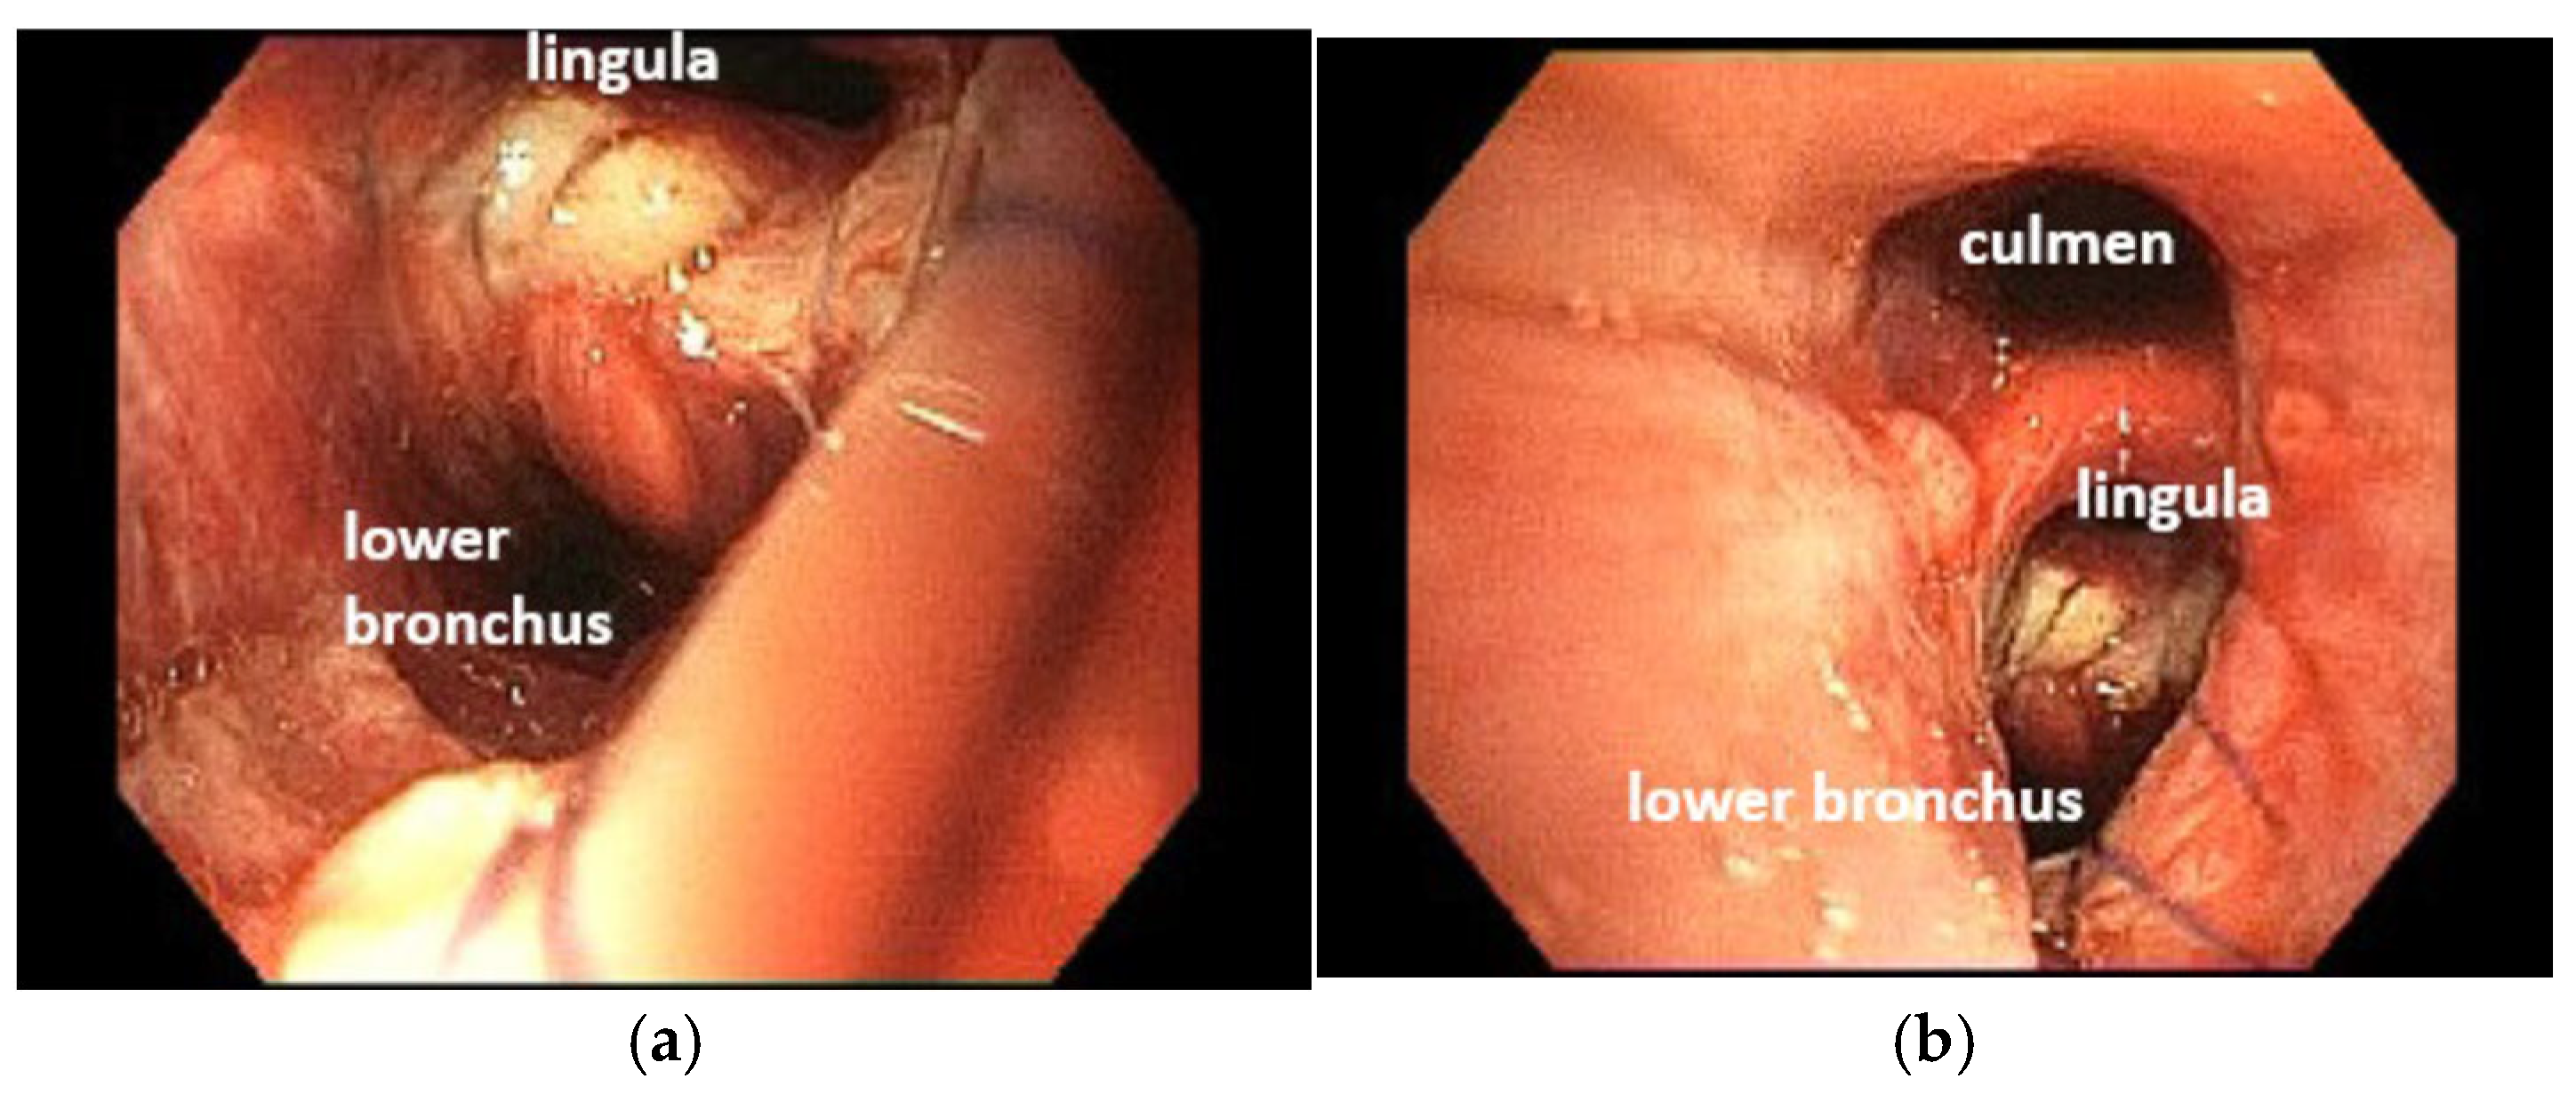

4.2. Case 2